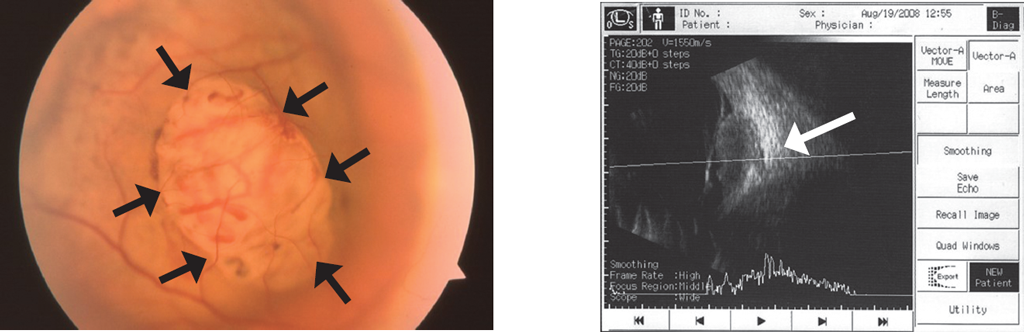

Figure 5 shows a typical astrocytoma of the optic nerve head, and Figure 6 shows amelanotic melanoma of the juxtapapillary localization. The most characteristic symptoms of astrocytoma are clear contours; yellow, orange, and pink color or a combination thereof; and multilobar structure (often having a mulberry shape). Retinal and optic head astrocytomas are most often observed in tuberous sclerosis complex but can also develop with type 1 neurofibromatosis or without any underlying medical condition [1, 2, 9, 14]. Typical astrocytoma of the optic nerve head often has a mulberry shape due to multiple calcification nodules. However, the fact that astrocytomas may not be accompanied by calcification sites [1, 2] should be remembered. Both tumors may be accompanied by secondary retinal detachment [2, 9]. Amelanotic melanoma with juxtapapillary localization can spread to the optic nerve head but does not directly originate from it, as in the clinical case presented. In addition to the typical lenticular form, melanoma can be fungiform (or take the form of a cufflink) due to the penetration of the Bruch’s membrane and infringement of the neoplasm apex in the defect [1]. Choroidal melanoma can often have two humps, indicating the presence of two growth epicenters, usually while developing from the previous nevus. However, we have never observed a multilobate structure of the choroidal melanoma. At the B-scan ultrasound imaging for vascular membrane melanoma, echogenicity is sub-average, sometimes with acoustic cavities and choroidal excavation [1, 2]. Melanoma can penetrate into the optic nerve head with circular growth, but the tumor prominence above it is not the highest.

Fig. 6. Amelanotic juxtapapillary choroidal melanoma penetrating Bruch’s membrane (black arrows). B-scan demonstrates deep choroidal excavation (white arrow)

Рис. 6. Беспигментная меланома хориоидеи юкстапапиллярной локализации с зоной прорастания мембраны Бруха (чёрные стрелки). При В-сканировании видна глубокая экскавация хориоидеи (белая стрелка)